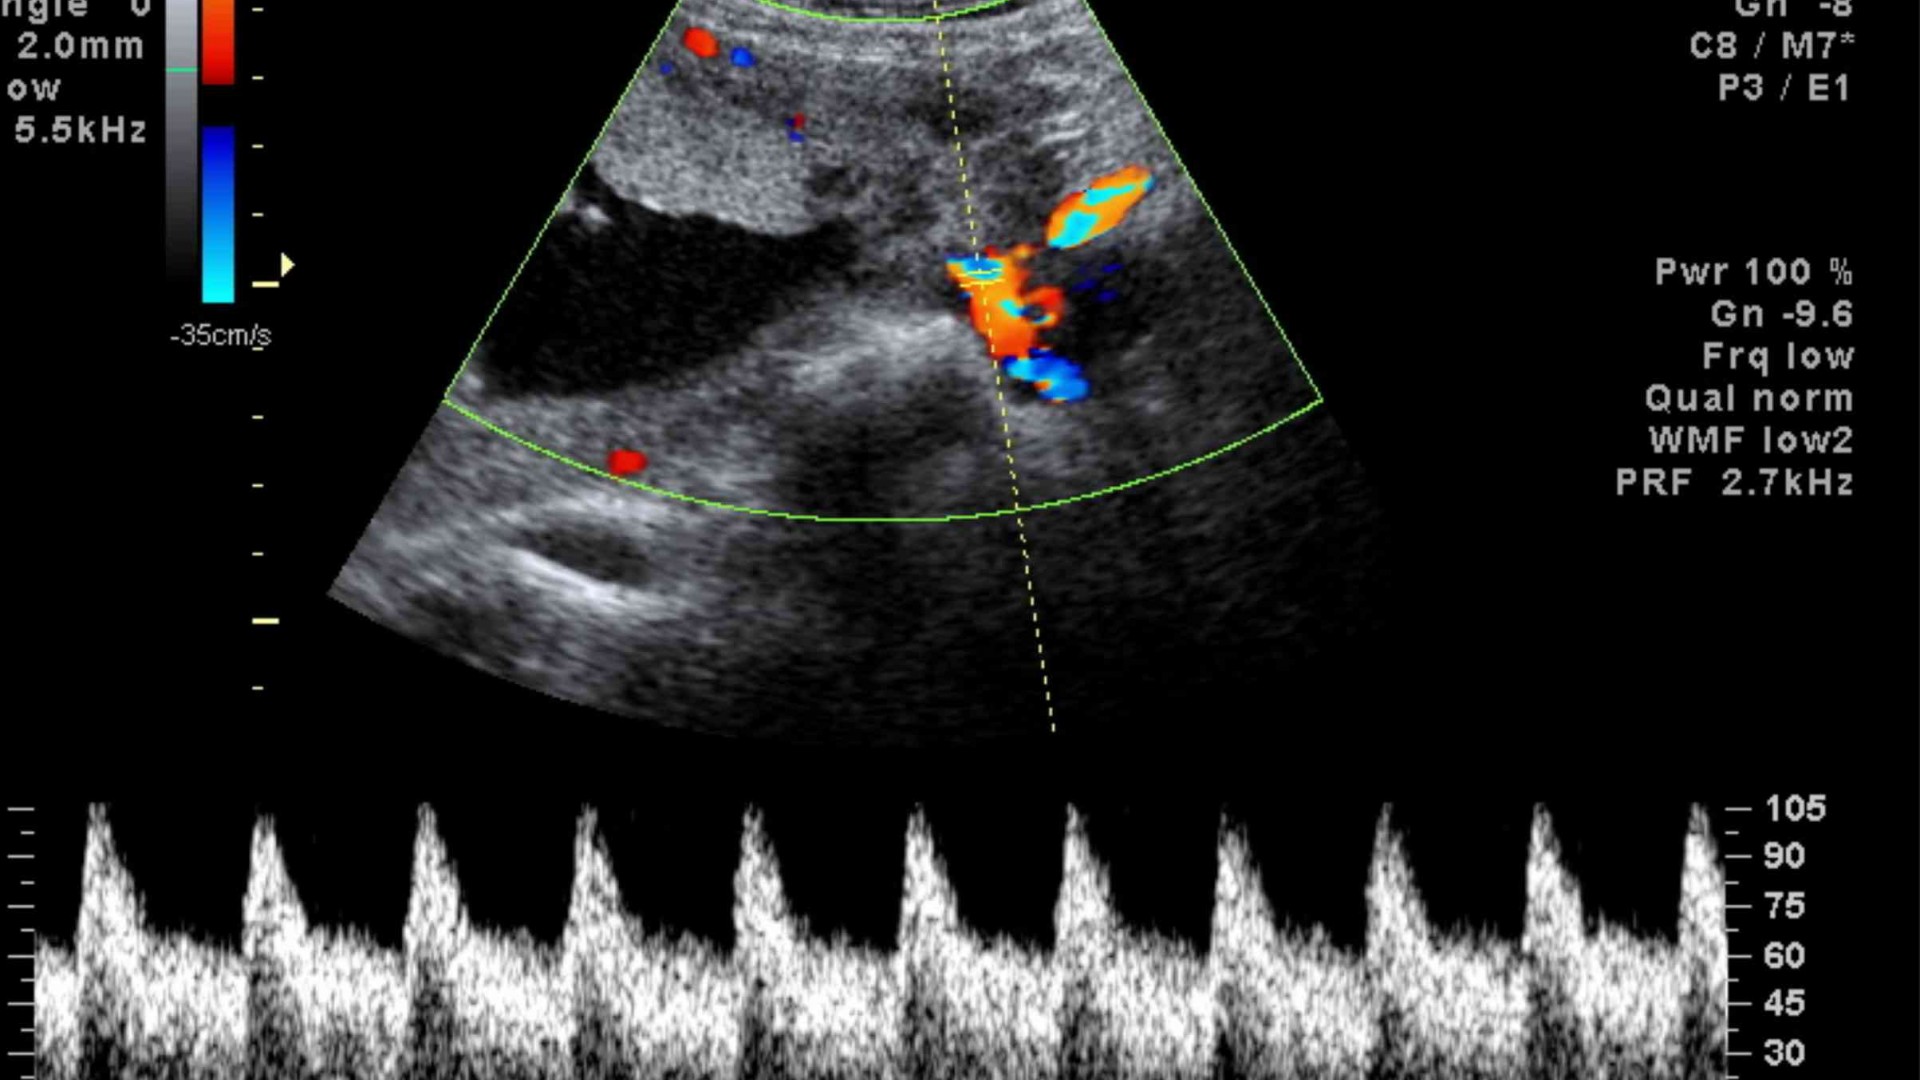

El diagnóstico exacto se hace a través del ecocardiograma (sumado al examen del médico y otros estudios como el electrocardiograma) y el tratamiento está a cargo del cardiólogo infantil.